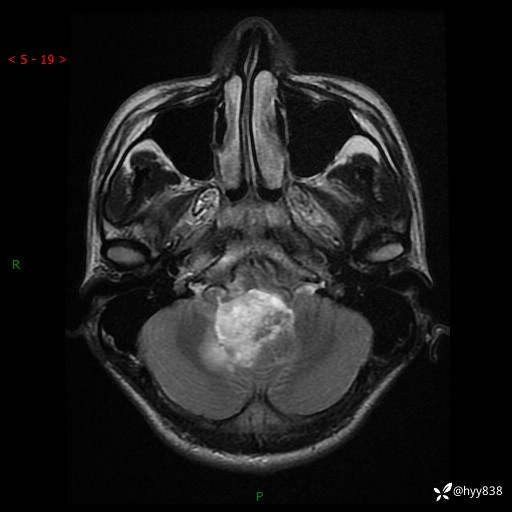

性别:男

年龄:17岁

简要病史:头痛伴间断性呕吐1月余,外院CT提示颅脑占位

颅脑MRI平扫+增强